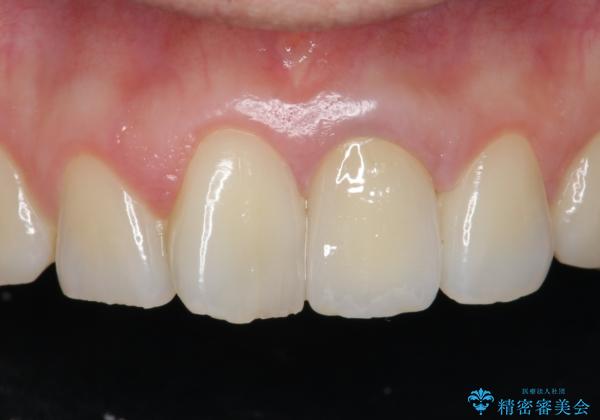

[ジルコニアクラウン] 前歯をきれいに

- 幼少時に行った前歯の治療、経年的に劣化し審美面の改善を求めて来院されました。

長期的な予後を見込むために、根管治療のやり直しから計画します。

- 13万円(仮歯・ファイバーコア・ジルコニアクラウン)費用は治療当時の料金となります

ジルコニアクラウンは色調を合わせることができるため、周囲の歯の色に調和し審美的な仕上がりを期待することができます。